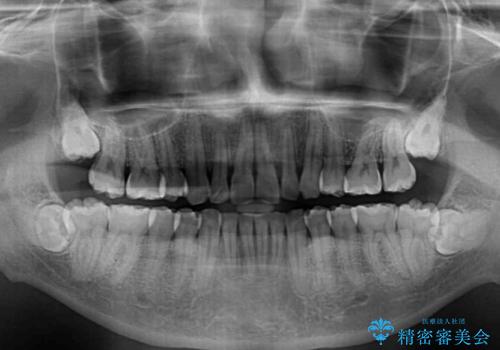

強い咬み込みですり減った前歯 デコボコを抜歯矯正で整える

口元の突出感はないものの、上顎前歯のデコボコが著しかったため、上顎左右第一小臼歯2本を抜歯することとしました。

咬合力が非常に強く、抜歯したスペースがなかなか閉じないであろうことは予想できましたが、思っていた以上に期間がかかりました。

前歯のすり減りも著しかったため、仕上げの位置の調整にも期間を要しました。